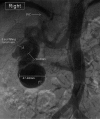

Renal artery aneurysms (RAAs) and renal arteriovenous fistulas (RAVFs) are rare lesions occurring in less than 1% of the population. Understanding treatment options is important in the care of these patients. Depending on the type of disease process, endovascular techniques, vascular bypass, renal autotransplantation, or nephrectomy may be indicated. The case reported describes a combined RRA and RAVF treated with nephrectomy.